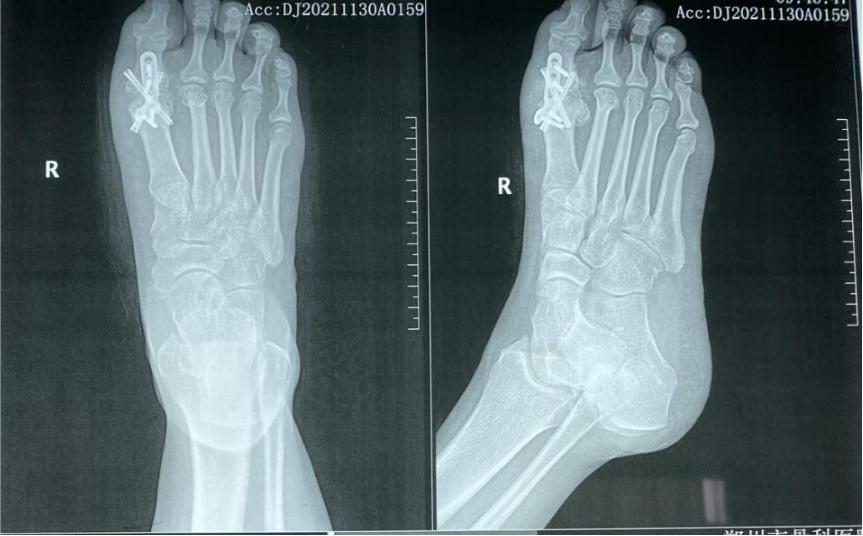

B. 跖骨翻修截骨术

由第一跖骨的畸形引发的拇内翻,是单纯肌腱手术纠正拇内翻的禁忌症。纠正跖骨力线异常需要截骨,并一定要联合应用肌腱转位术。

4. 注意合并的外侧组织内翻畸形

如果踇趾明显内翻,时间长了会牵拉外侧足趾的内翻,踇趾畸形纠正后,外侧足趾不能够恢复正常,需要行关节囊切开和松解内侧副韧带,如果仍不能够纠正畸形,需要短缩跖骨才能达到理想效果,相当于间接延长了内在肌,从而松解了挛缩的组织。